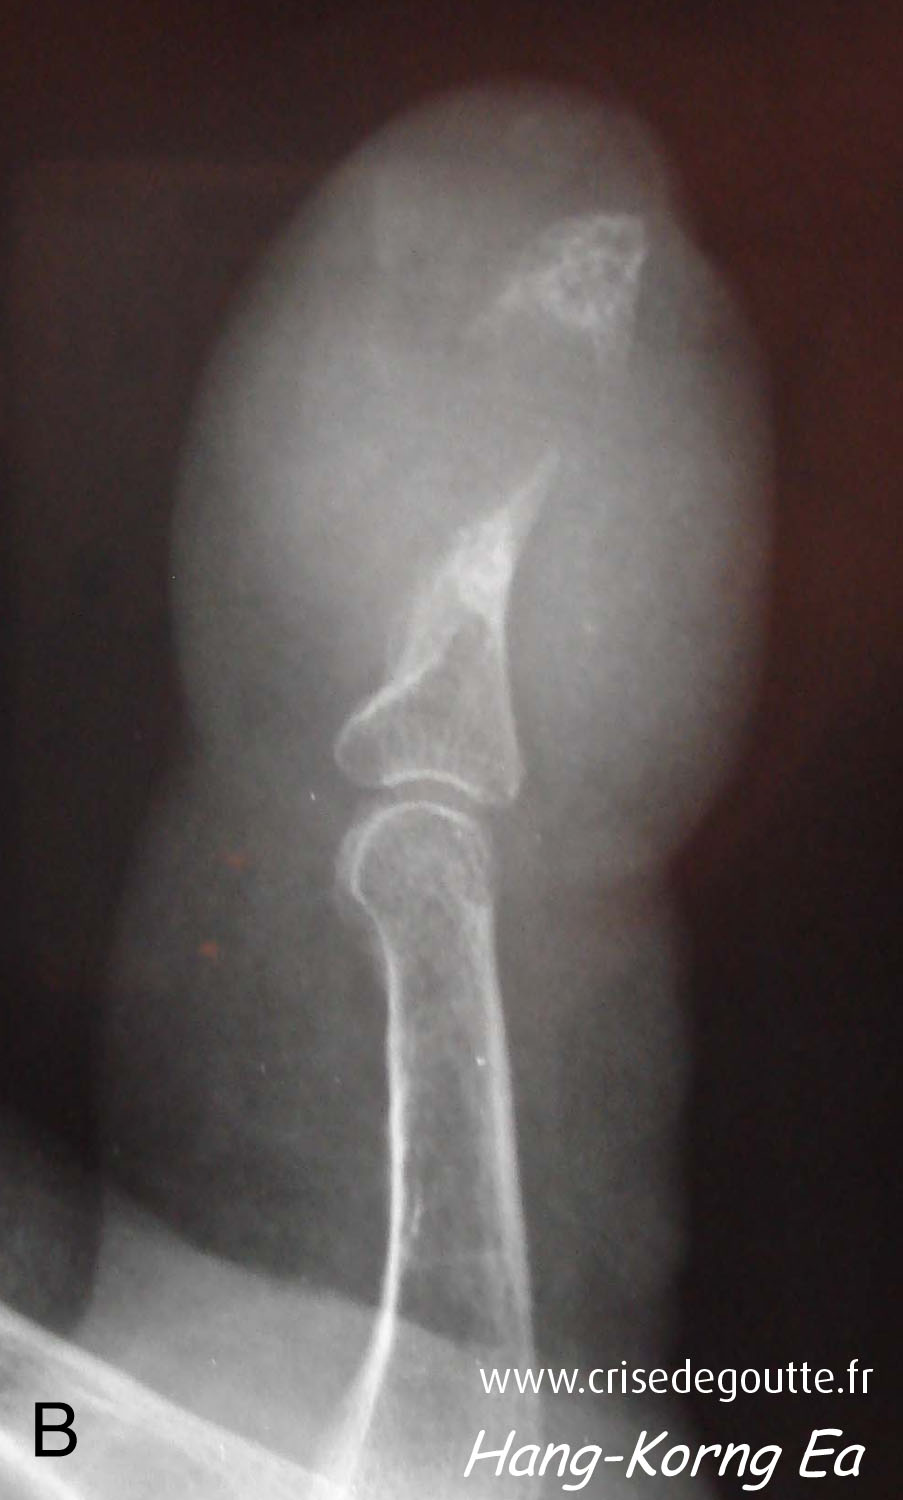

Imagerie

Tophus